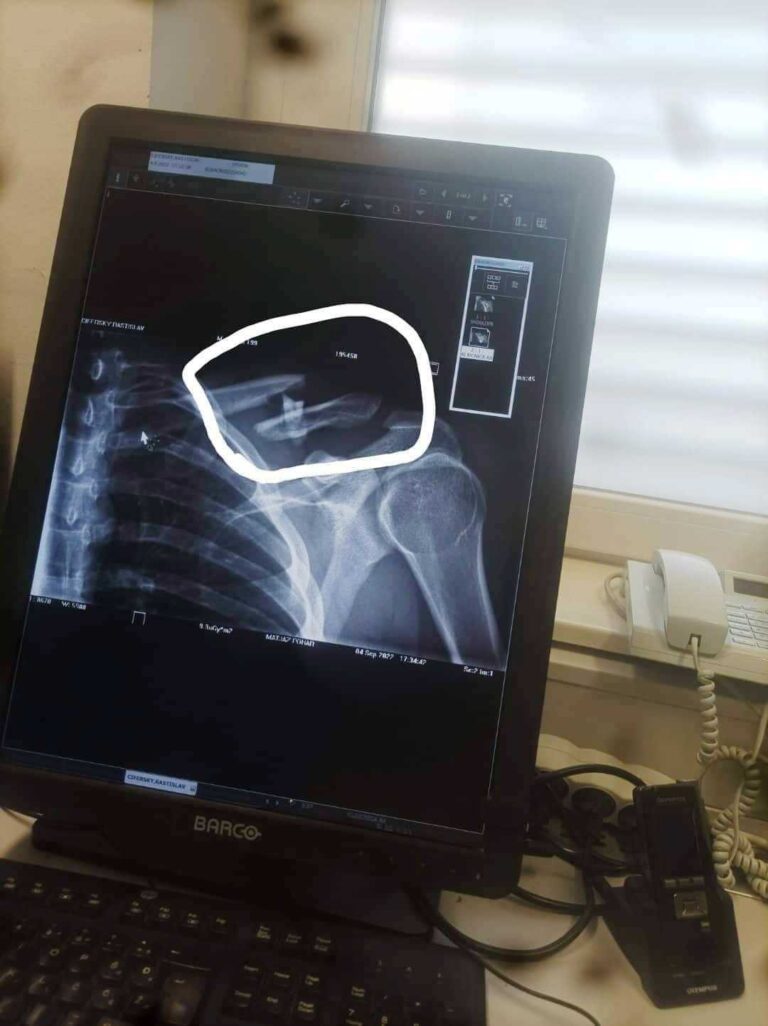

Rasťo Cíferský podstúpil operáciu

Ešte v nedeľu 4. septembra si pri páde v slovinskom Kršku v prvej jazde 1.ligy privodil zlomeninu kľúčnej kosti jeden z našich pretekárov Rastislav Cíferský.